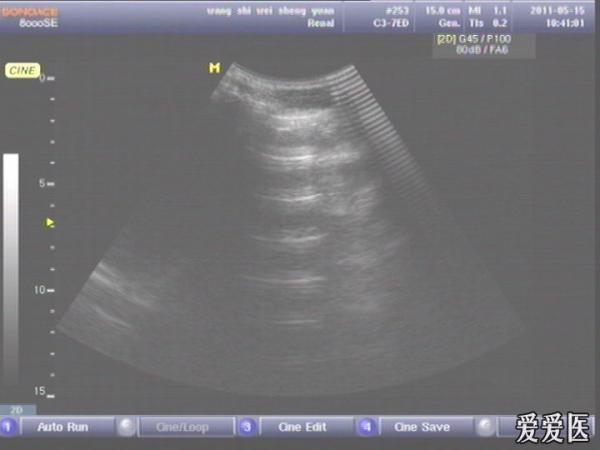

患者,男,38岁,进食后突发上腹部持续性剧烈疼痛一小时来查。超声见横膈与肝之间、上腹部皮下气体强反射回声,后伴多重反射,肝前、肝肾间隙,腹腔肠管间均可见游离无回声区。直视腹部见上腹部似板样。结合病史提示“胃肠道穿孔”。急诊手术证实。

左肝外叶的那个切面如果能看到气体回声的话,那就应该高度怀疑这个病了。好切面,好好学习,太有用了,楼主辛苦感谢感谢。